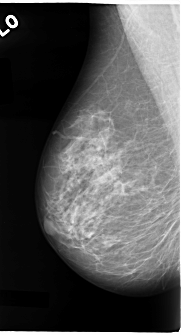

C_0087_1.RIGHT_MLO

LEFT_MLO LINES 4824 PIXELS_PER_LINE 2936 BITS_PER_PIXEL 12 RESOLUTION 50 OVERLAY

FILE: C_0087_1.LEFT_MLO.OVERLAY

TOTAL_ABNORMALITIES 3

ABNORMALITY 1

LESION_TYPE CALCIFICATION TYPE PLEOMORPHIC DISTRIBUTION CLUSTERED

ASSESSMENT 5

SUBTLETY 5

PATHOLOGY MALIGNANT

TOTAL_OUTLINES 1

ABNORMALITY 2

ABNORMALITY 3